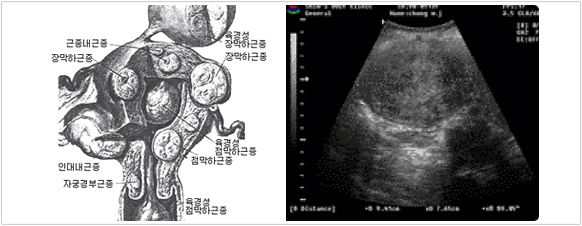

ÀڱñÙÁ¾À̶õ?

• ÀڱñÙÁ¾À̶õ ÀÚ±ÃÀÇ ±ÙÀ°À» ÀÌ·ç°í ÀÖ´Â "ÆòȰ±Ù"¿¡¼­ ±â¿øÇÏ´Â ¾ç¼ºÁ¾¾çÀÔ´Ï´Ù.

• ÀÌ ÁúȯÀº ¸Å¿ì ÈçÇÑ ÁúȯÀ¸·Î °¡ÀÓ¿©¼ºÀÇ ´ëºÎºÐÀÌ °æÇèÇÏ´Â º´ÀÔ´Ï´Ù.

ÀڱñÙÁ¾À̶õ ÀÚ±ÃÀÇ ±ÙÀ°ÀÌ ¹¶ÃÄ È¤ÀÌ ¸¸µé¾îÁö´Â ÁúȯÀÔ´Ï´Ù. ÀڱñÙÁ¾Àº ¹ß»ýÀ²ÀÌ 20% Á¤µµ·Î, °¡Àӱ⠿©¼º¿¡°Ô ¸Å¿ì ÈçÇÑ Áúȯ Áß¿¡ ÇϳªÀÔ´Ï´Ù. ÀڱñÙÁ¾Àº ¾ÏÀÌ ¾Æ´Ñ ¾ç¼ºÀÇ È¤À¸·Î ¡°»ì Ȥ ȤÀº ¹° Ȥ¡±À̶ó°í ºÒ¸®±âµµ ÇÕ´Ï´Ù.